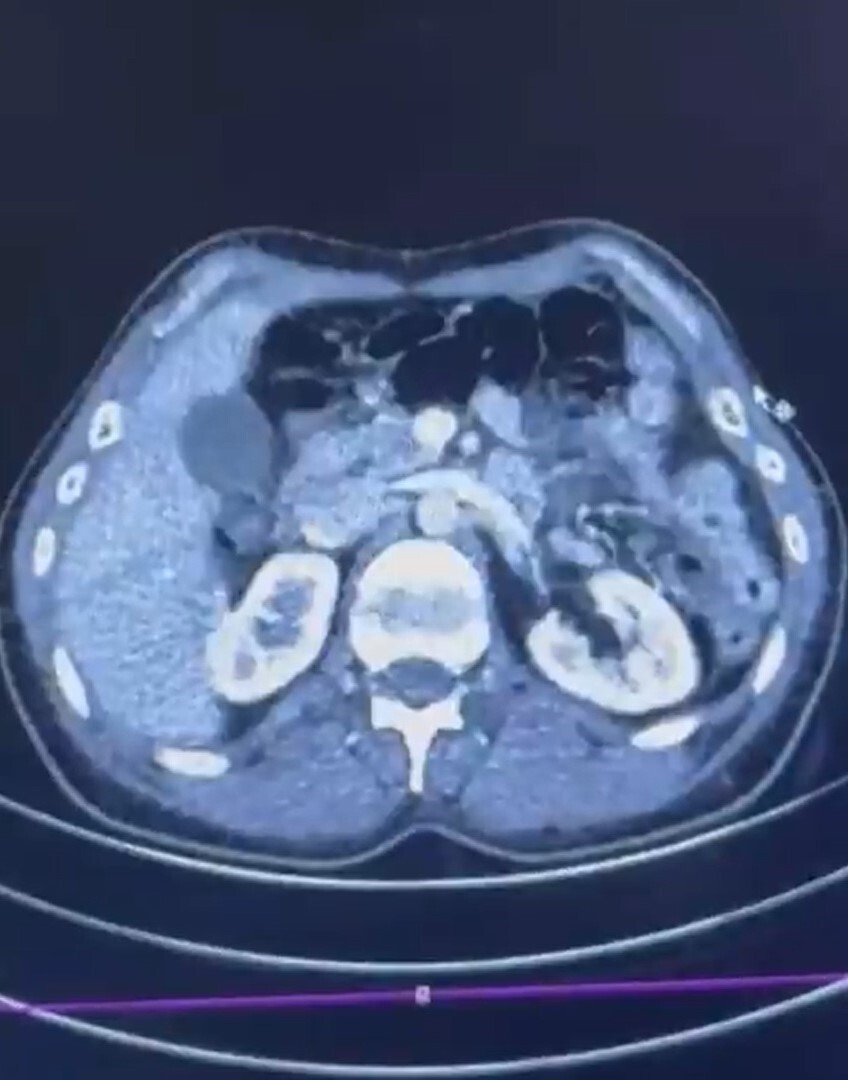

Kayseri Şehir Hastanesi'nde yapılan iç beden muayenelerinde, şüphelilerin mide kısmında 50 adet kapsül halinde toplam 554 gram uyuşturucu madde bulunduğu tespit edildi.

ŞÜPHELİLERİN MİDESİNDE KAPSÜL ŞEKLİNDE YARIM KİLO UYUŞTURUCU MADDE ELE GEÇİRİLDİ.